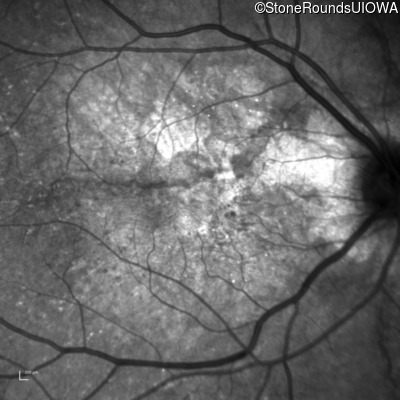

Visit at age: 62 years (Visit 3)

Optical Coherence Tomography - Right - 20/80

Exemplar / OCT Stack

Infrared Fundus Photograph - Right - 20/80

Exemplar